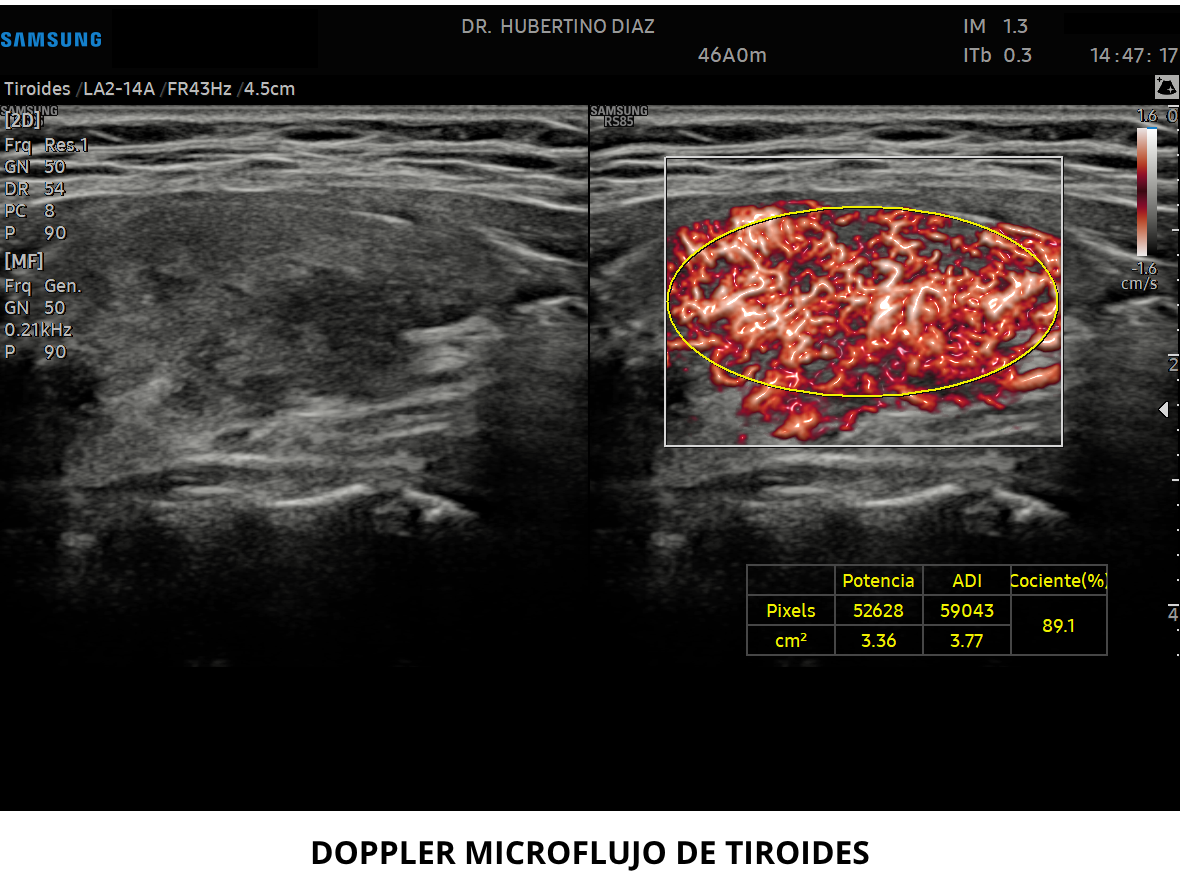

• Doppler microvascular de tiroides